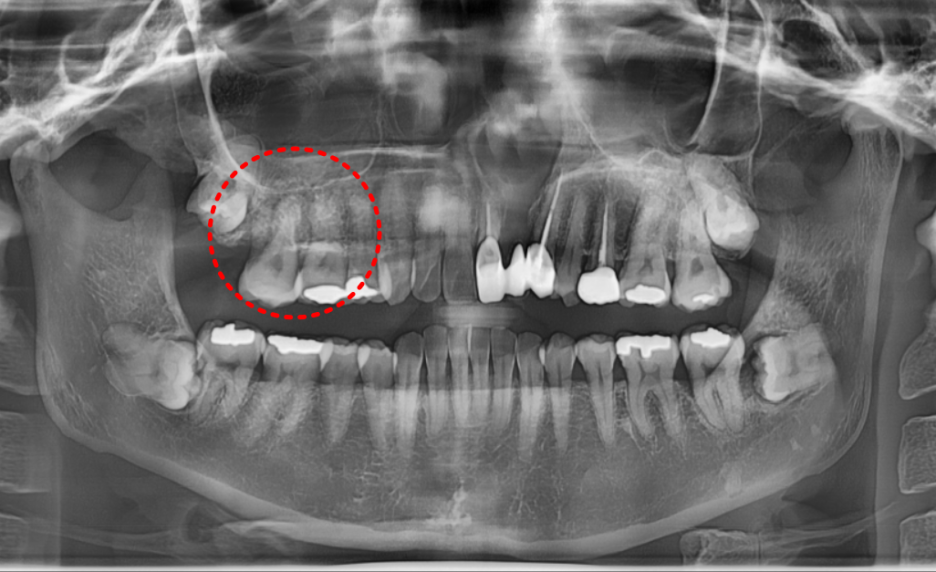

이번 환자분은

오른쪽 위 어금니 2개가 시간이 지나면 지날수록 흔들림이 심해진다고 하셨습니다.

250121

조금 더 정밀한 사진 촬영을 해 보니 (ct) 상황은

예상보다 심각했습니다.

뿌리 사이에 염증이 깊숙이 퍼져 있었고,

치아를 지탱하는 주변 뼈가 이미 상당 부분 손실된 상태였습니다.

게다가 입천장의 절반 이상이 심하게 부어올랐고,

잇몸에서는 고름이 나오고 있었습니다.